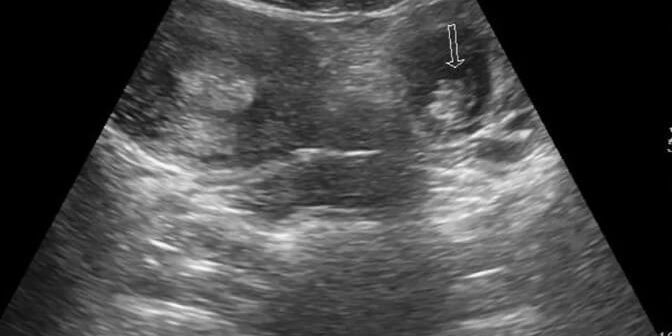

Untuk membedakan antara kehamilan normal dan kehamilan ektopik, tidak dapat diketahui begitu saja secara kasat mata. Apalagi tidak ada ciri – ciri khusus yang terlihat pada jenis kehamilan ini. Jenis kehamilan ektopik hanya dapat diketahui dari pemeriksaan medis. Salah satunya dengan USG.